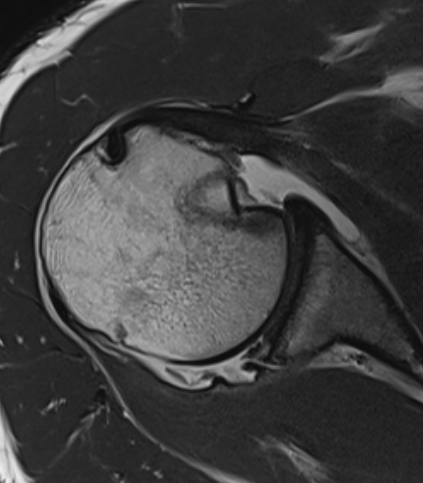

MRI

Chronic posterior shoulder dislocation with humeral head remodelling and glenoid bony deficiency